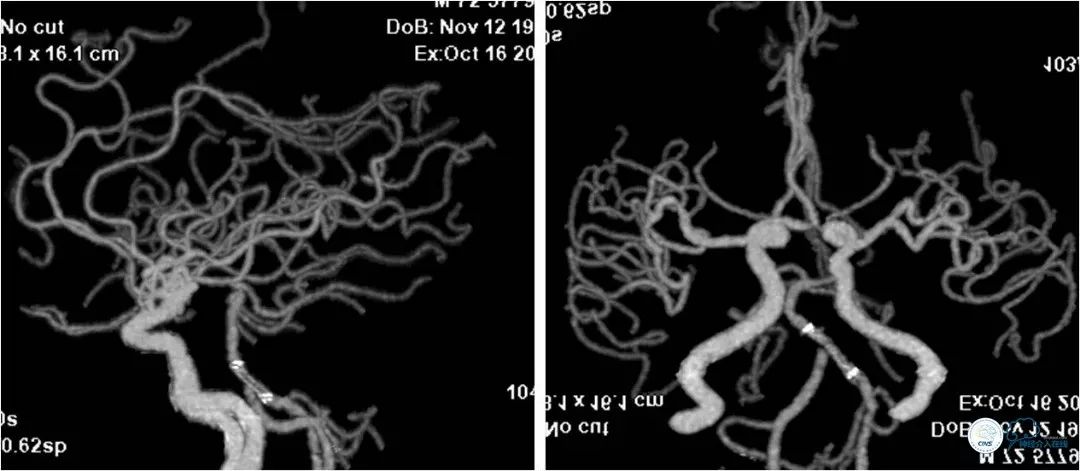

DSA提示:左椎动脉开口迂曲,右椎动脉开口中度狭窄(图5)。双椎动脉V4段与基底动脉交界处重度狭窄,左侧狭窄程度更重(图6,7)。

图5

图6

图7

对双椎动脉V4段-基底动脉交界区重度狭窄进行血管内介入治疗干预,我们会根据入路迂曲与否,病变远近正常血管的直径,病变是否成角等诸多因素选择治疗路径和介入器械。本例患者右椎动脉稍粗,但右椎V4段-基底动脉汇合处病变成角,支架放置后有可能贴壁不佳,故选择治疗路径上较为平顺的左椎入路,以期减少相关血管损伤。